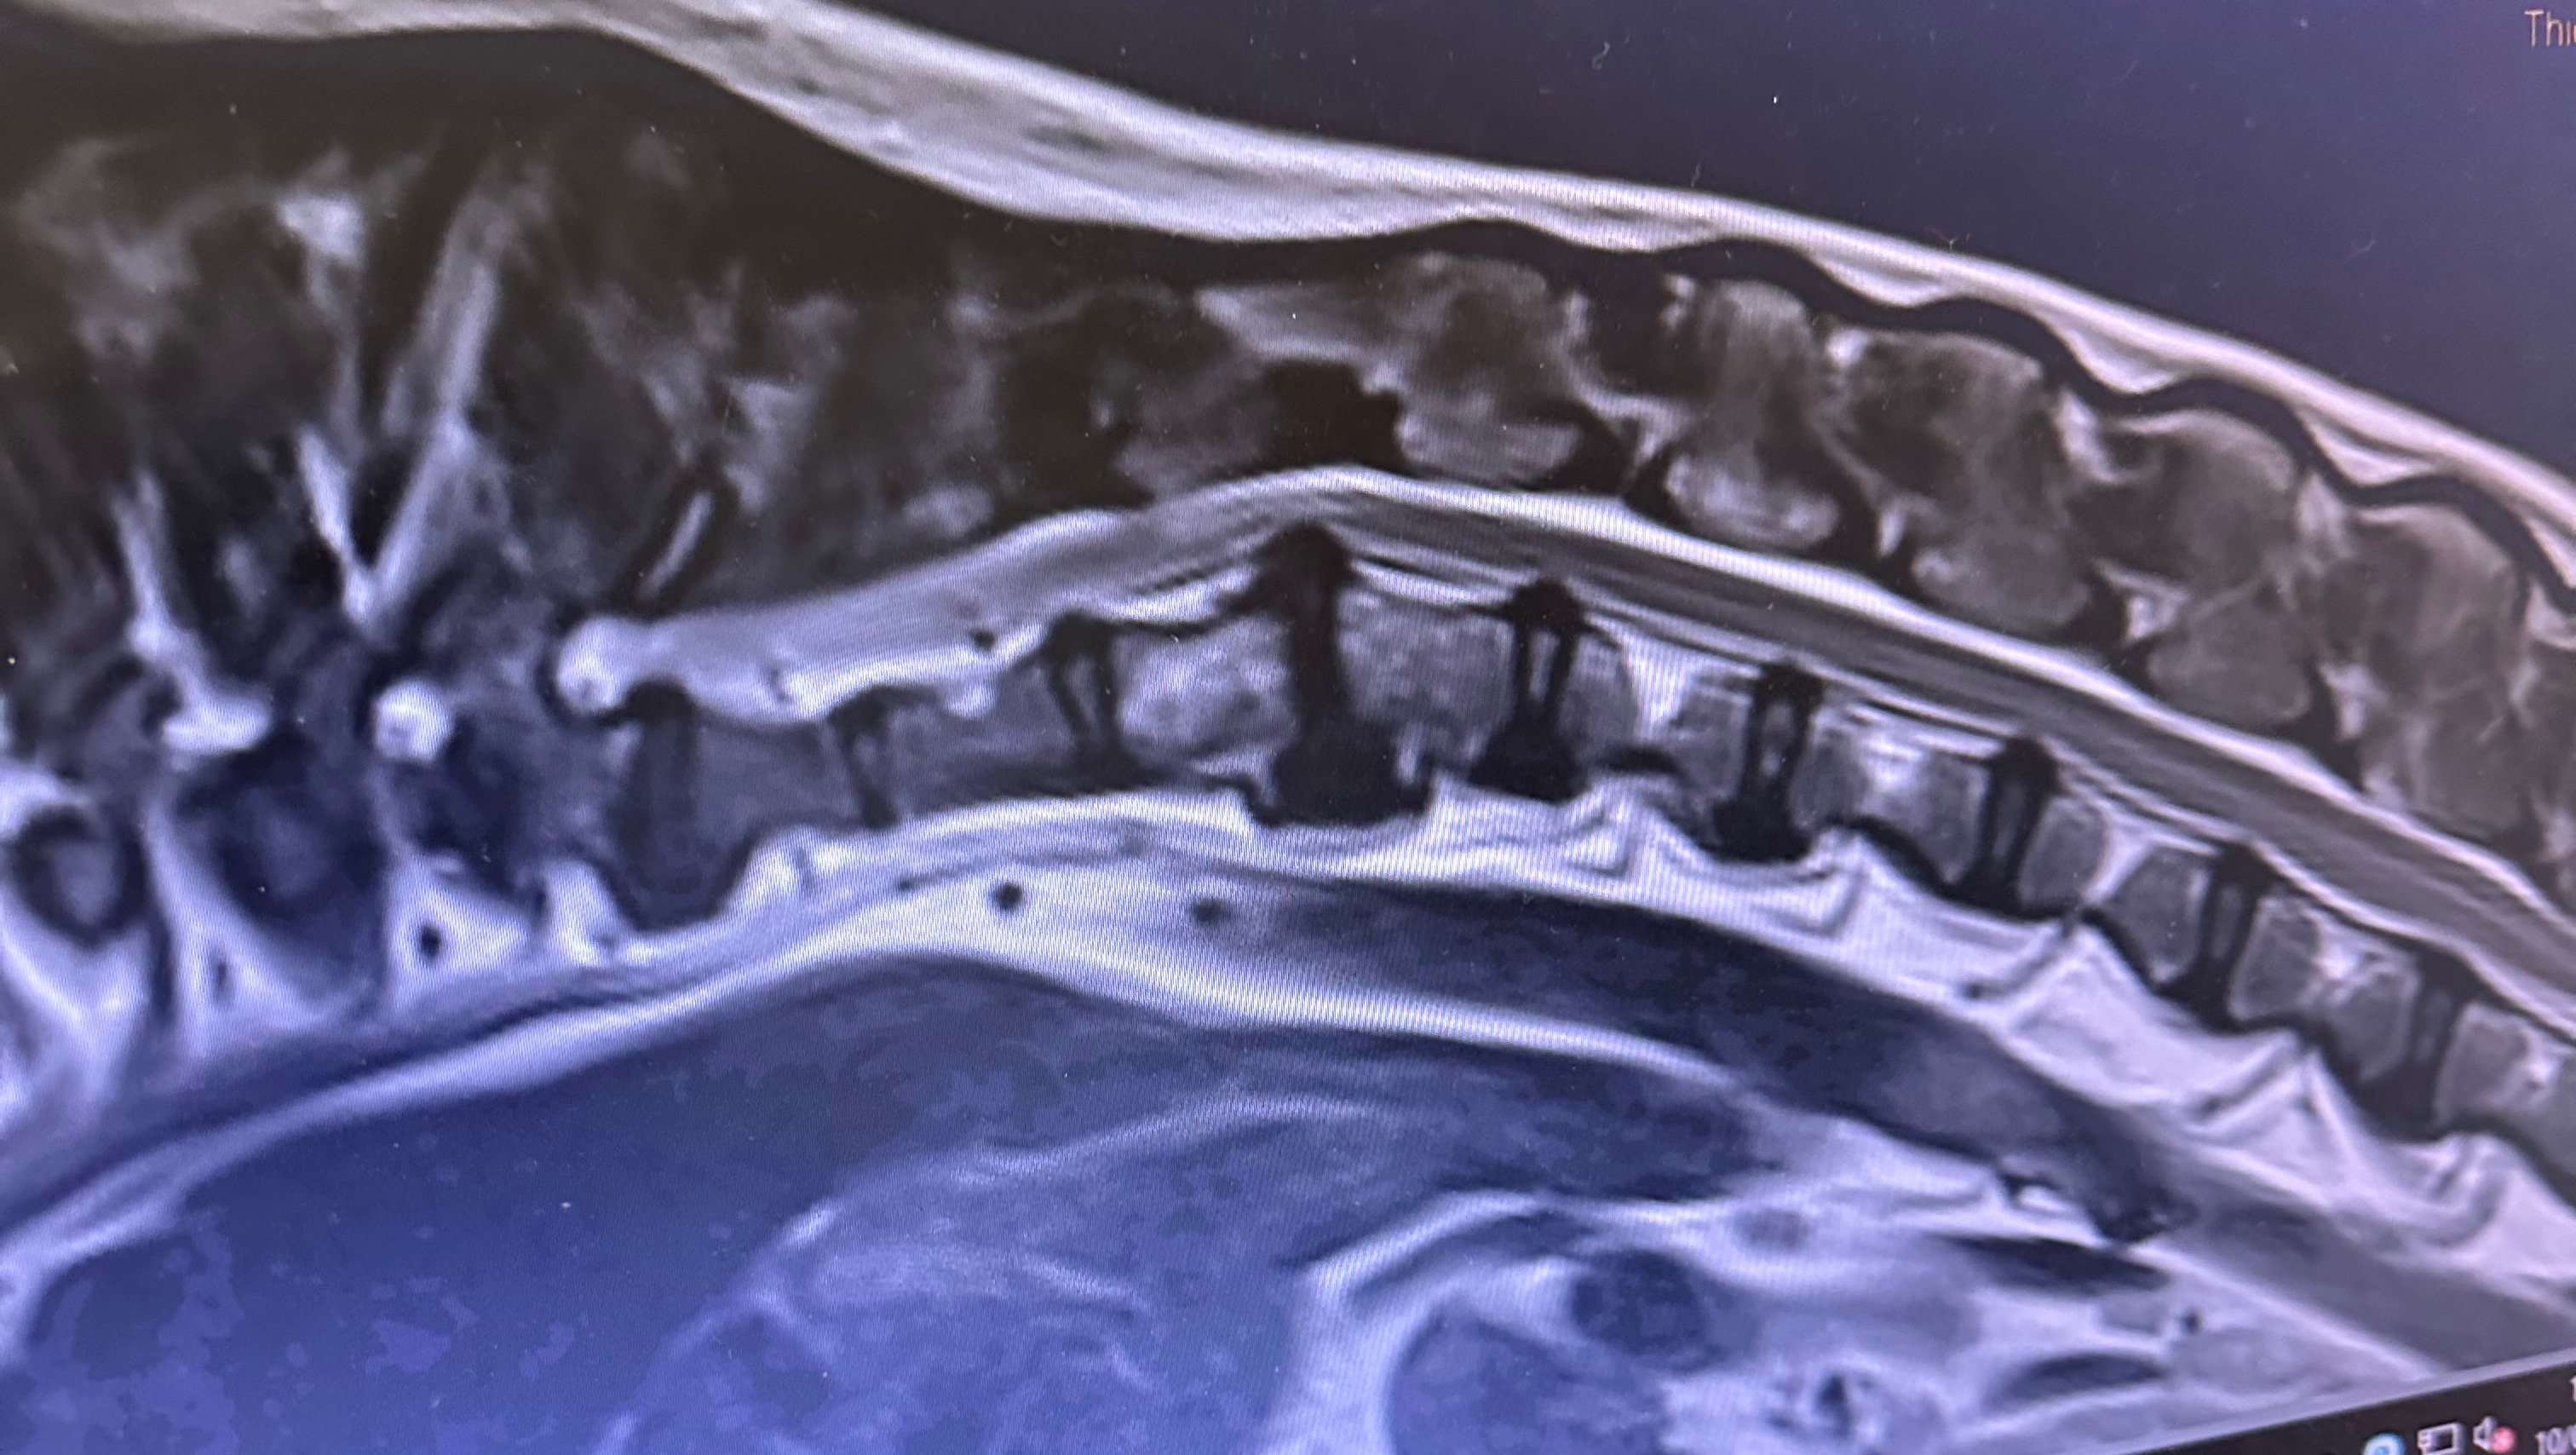

One of the major heath issues he’s dealing with is the horrendous Intervertebral Disc Disease (IVDD) on his spine.

At the beginning of this year, Arlos IVDD appeared near his neck and one of the discs burst, causing him a lot of pain and not being able to move properly. He then had an MRI, then urgently leading to surgery which he is now recovering from.

Upon our post-op check, the vet informed us of another complication on Arlos MRI scan: There is another disc in the middle of his back that is bulging and is a ticking time bomb from bursting, but this time it’s right on his spinal cord which could cause paralysis or worse.